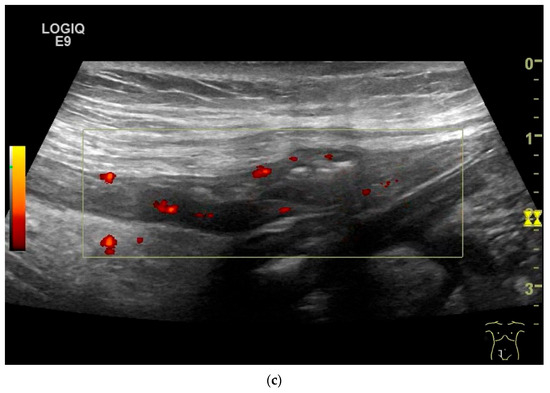

Figure 8.

NET in the ileum. In the terminal ileum, there is a slight wall thickening <5 mm (arrow), but with loss of stratification (a). The tumor (arrow) changes position with peristalsis while the transducer position remains the same. With the 9 MHz linear transducer, the five layers of the unremarkable wall and Kerckring folds (KF) are visible (b). Small vessels can be distinguished in power Doppler (c).